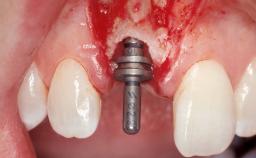

Type of Implants One-Piece

Attachment One-Piece

Placement Protocol Early or late implant placement

Loading Protocol Conventional or early

Provisional Implant-Supported Prosthesis Prosthodontic margin < 3 mm apical to mucosal margin Prosthodontic margin < 3 mm apical to mucosal margin